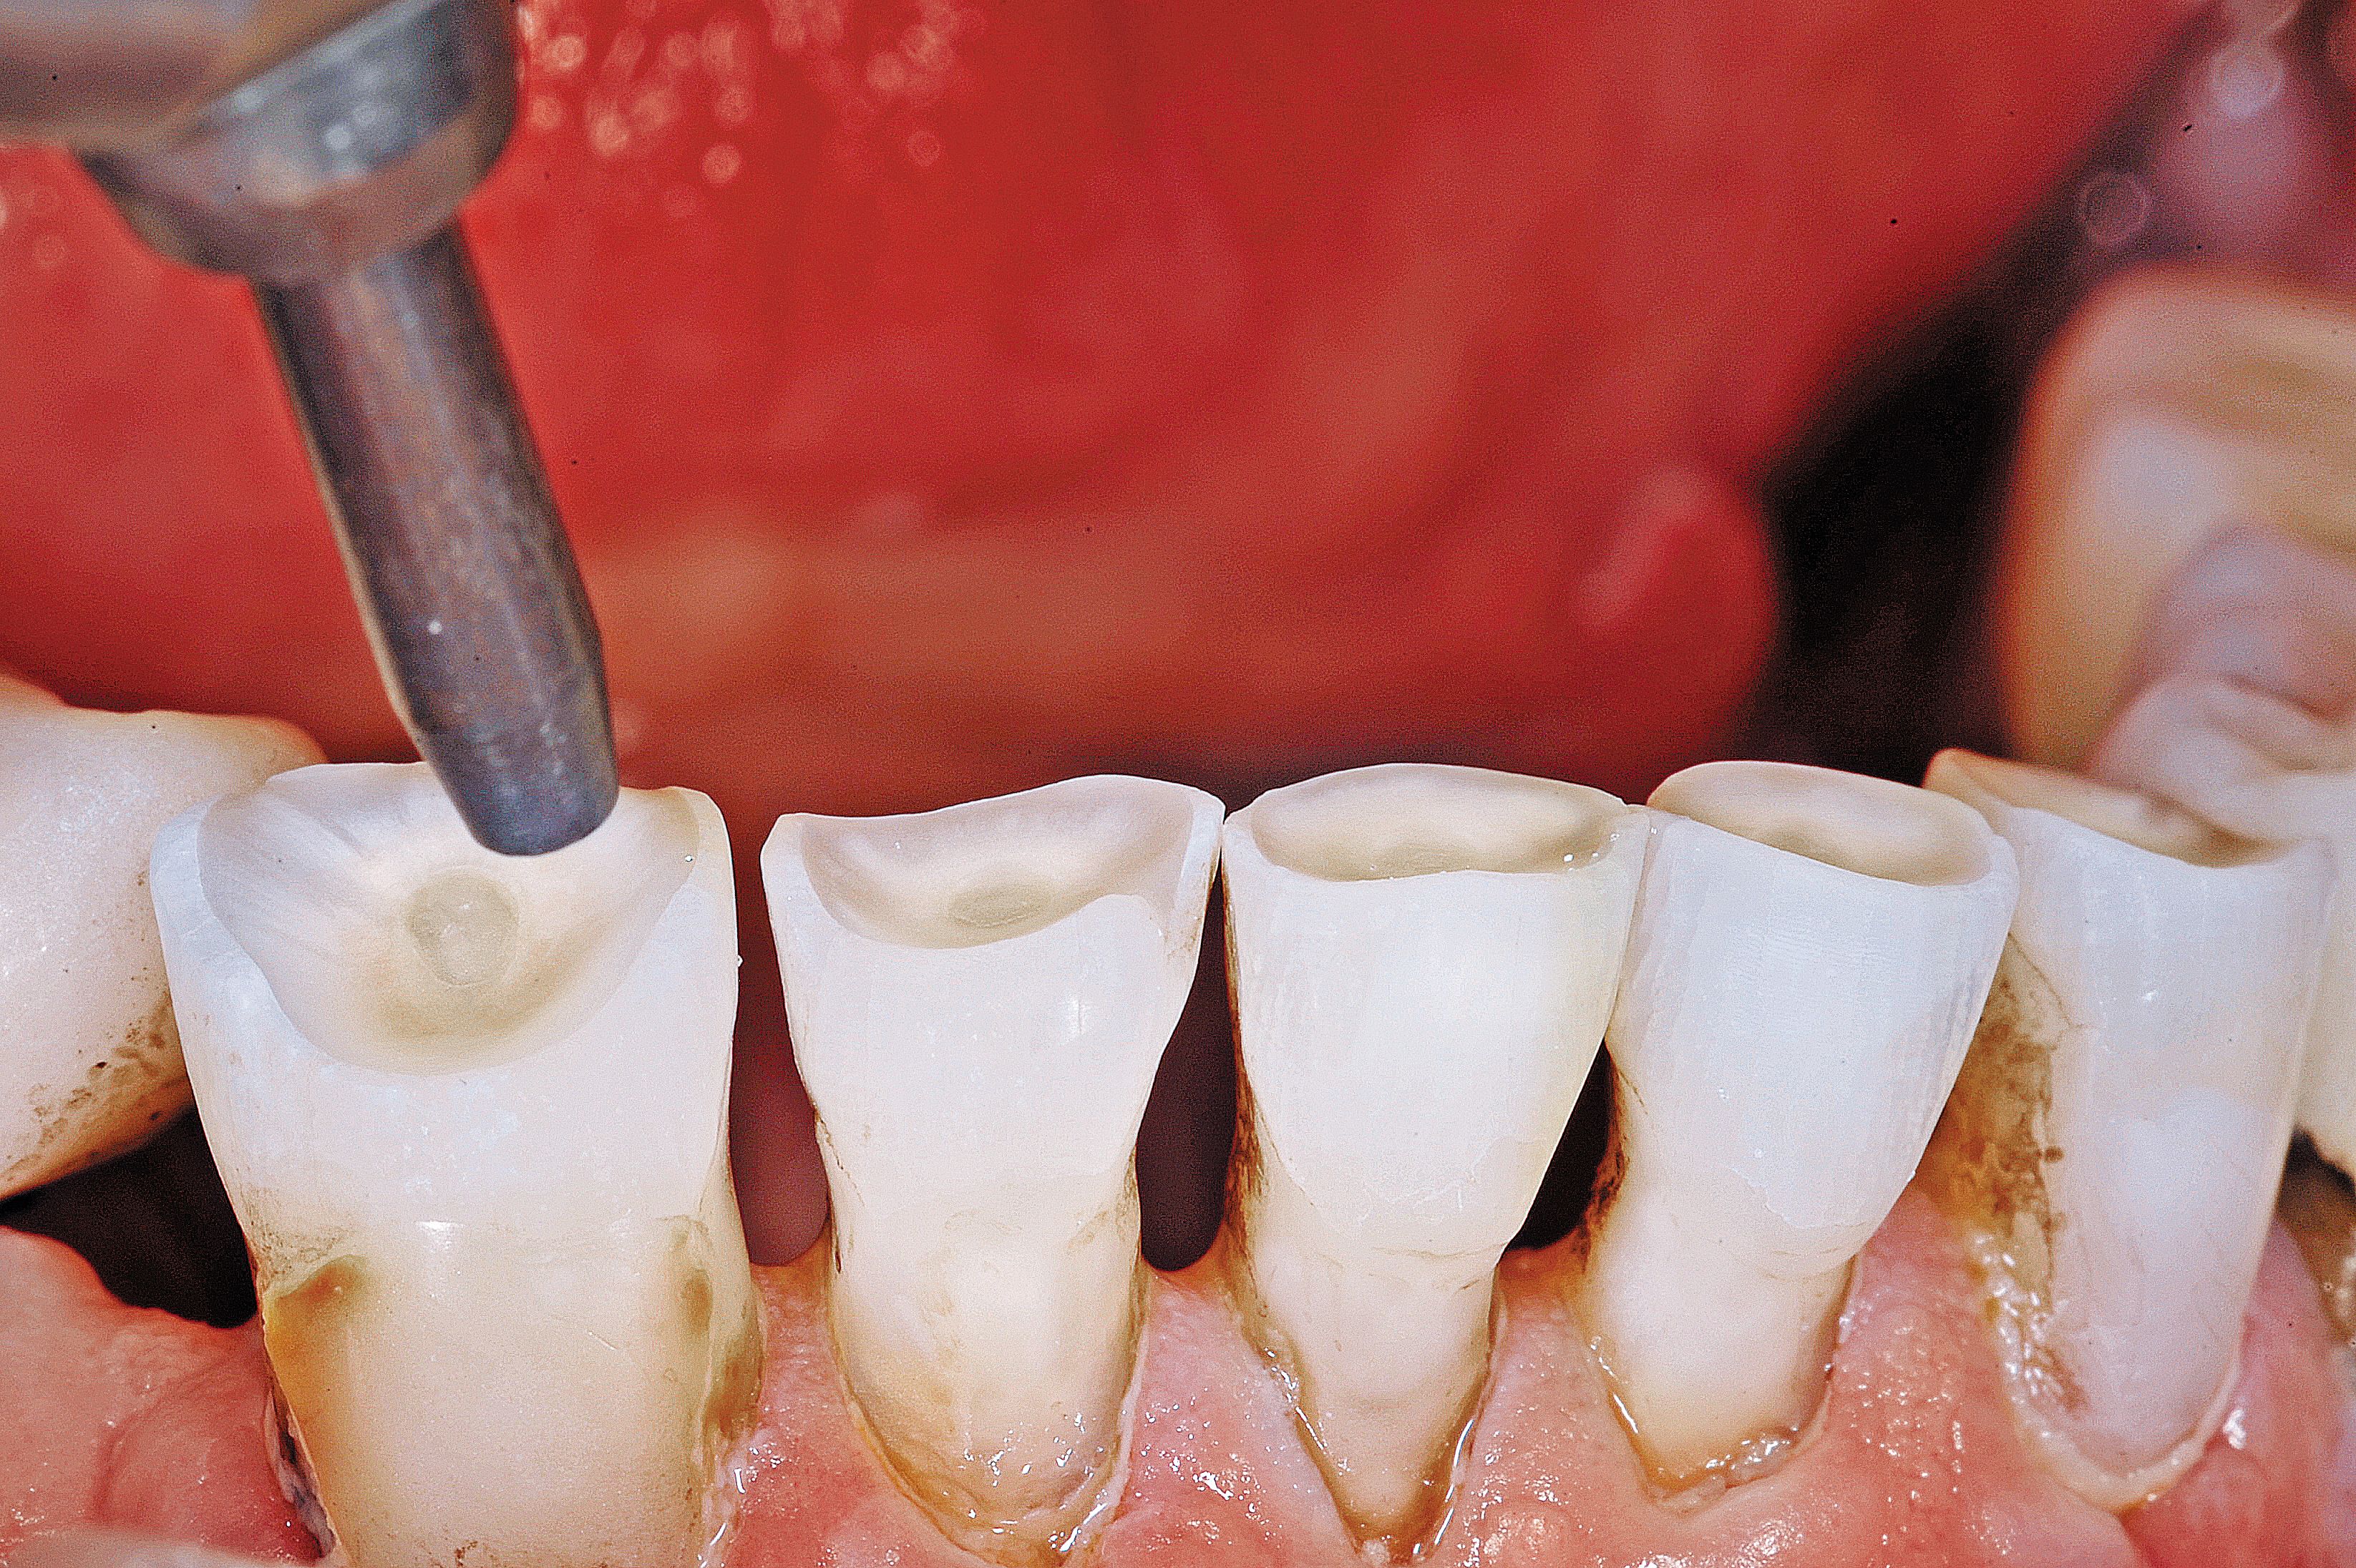

Fig. 2

The wear of the opposing denture and acrylic teeth was significant enough to see the secondary dentin of the pulp.